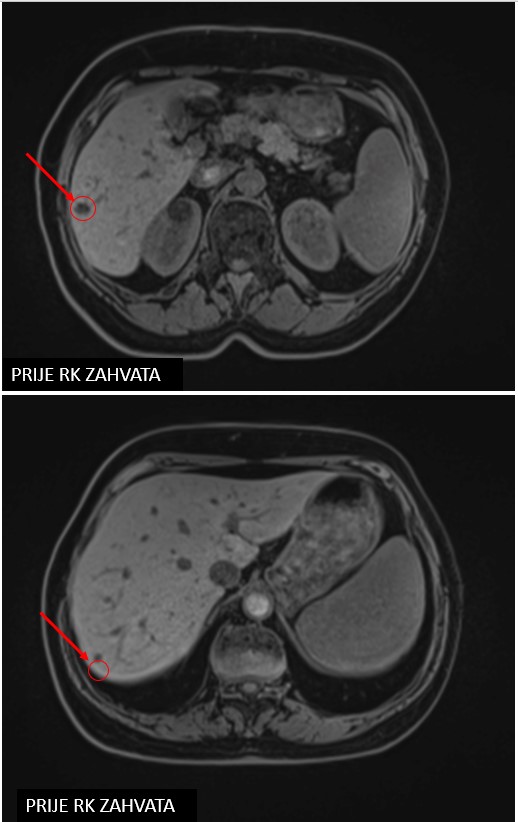

Meta hepatis

SBRT meta hepatis (07/2020, 10/2020, 06/2021, 10/2021, 06/2022)

Rezultat – 35 mjeseci nakon RK

Potpuni nestanak tretiranih lezija